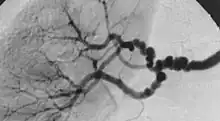

The "string-of-beads" feature in multi-focal fibromuscular dysplasia. The sign is caused by areas of relative stenoses alternating with small aneurysms.

Multi-focal (previously known as medial) fibroplasia involves thickening of the media and collagen formation. It is typically reported as having the appearance of a "string of beads" on angiographic review.[4] "The 'bead' component is often larger than the normal arterial lumen, and in a subset of patients with FMD, aneurysms are present that may require treatment."[4] The multi-focal subtype of FMD accounts for nearly 80% to 90% of all FMD cases.[4]